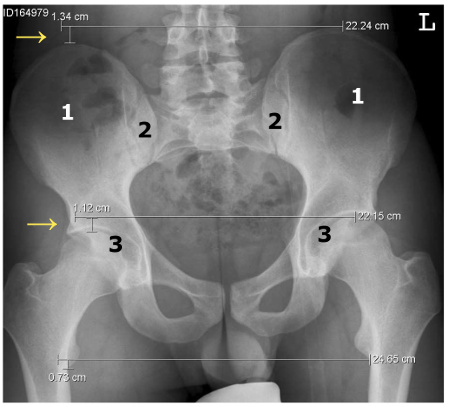

Ausgangspunkt vieler Beschwerden im Bewegungsapparat ist das Becken. Es besteht aus den beiden Hüftbeinen (siehe "1" auf dem Röntgenbild unten), die über das Iliosakralgelenk (ISG, siehe "2") mit dem Kreuzbein verbunden sind. Bei der Beckenverwringung sind die beiden Hüftbeine gegeneinander verdreht. Dies führt zu einer veränderten Lage der beiden Hüftgelenkspfannen (siehe "3"), weshalb ein Bein kürzer als das andere erscheint (siehe "→"). Man spricht von einer funktionellen Beinlängendifferenz. Das ist ein scheinbarer Unterschied der Beinlängen infolge einer Fehlstellung des Beckens und der Wirbelsäule - im Gegensatz zu einer anatomischen Beinlängendifferenz, bei der die Beine tatsächlich verschieden lang sind.

Die Beckenverwringung führt aber nicht nur zu scheinbar verschieden langen Beinen, sondern auch zur Fehlstellung des Kreuzbeins und der Wirbelsäule, was sich bis hinauf zu den Halswirbeln negativ auswirken kann.